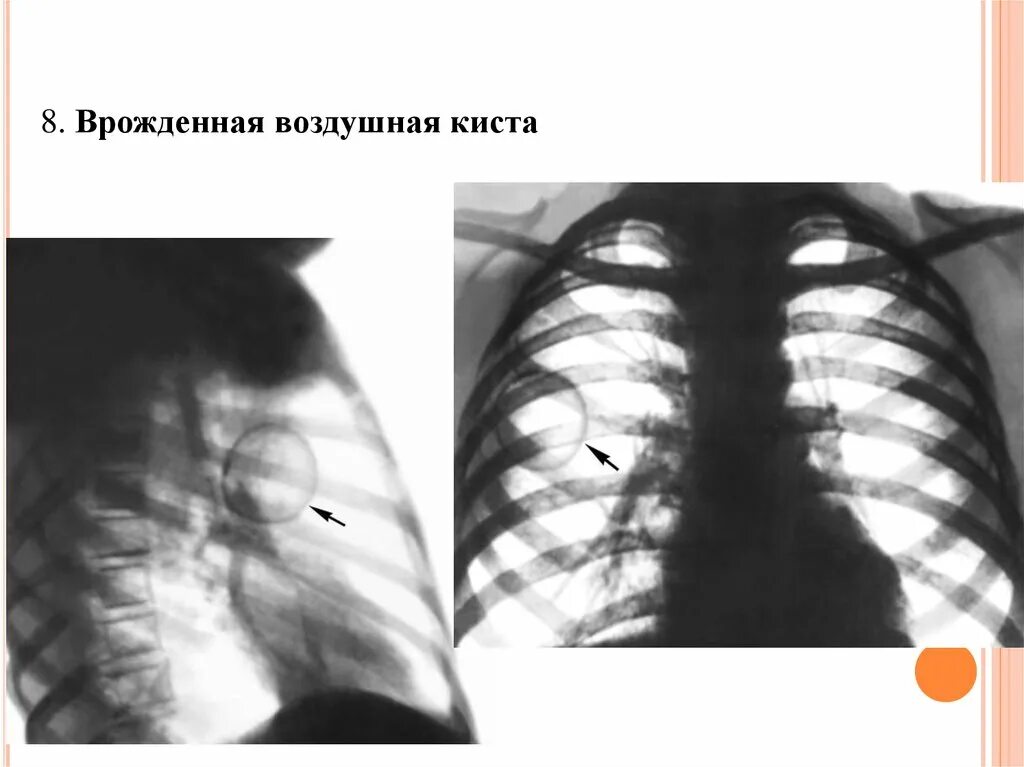

Аномалии органов дыхания